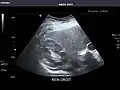

Right kidney -

Kidneys: Right and left kidneys measure 11.5 cm and 12 cm in length respectively. No hydronephrosis. Small left lower pole kidney cyst.